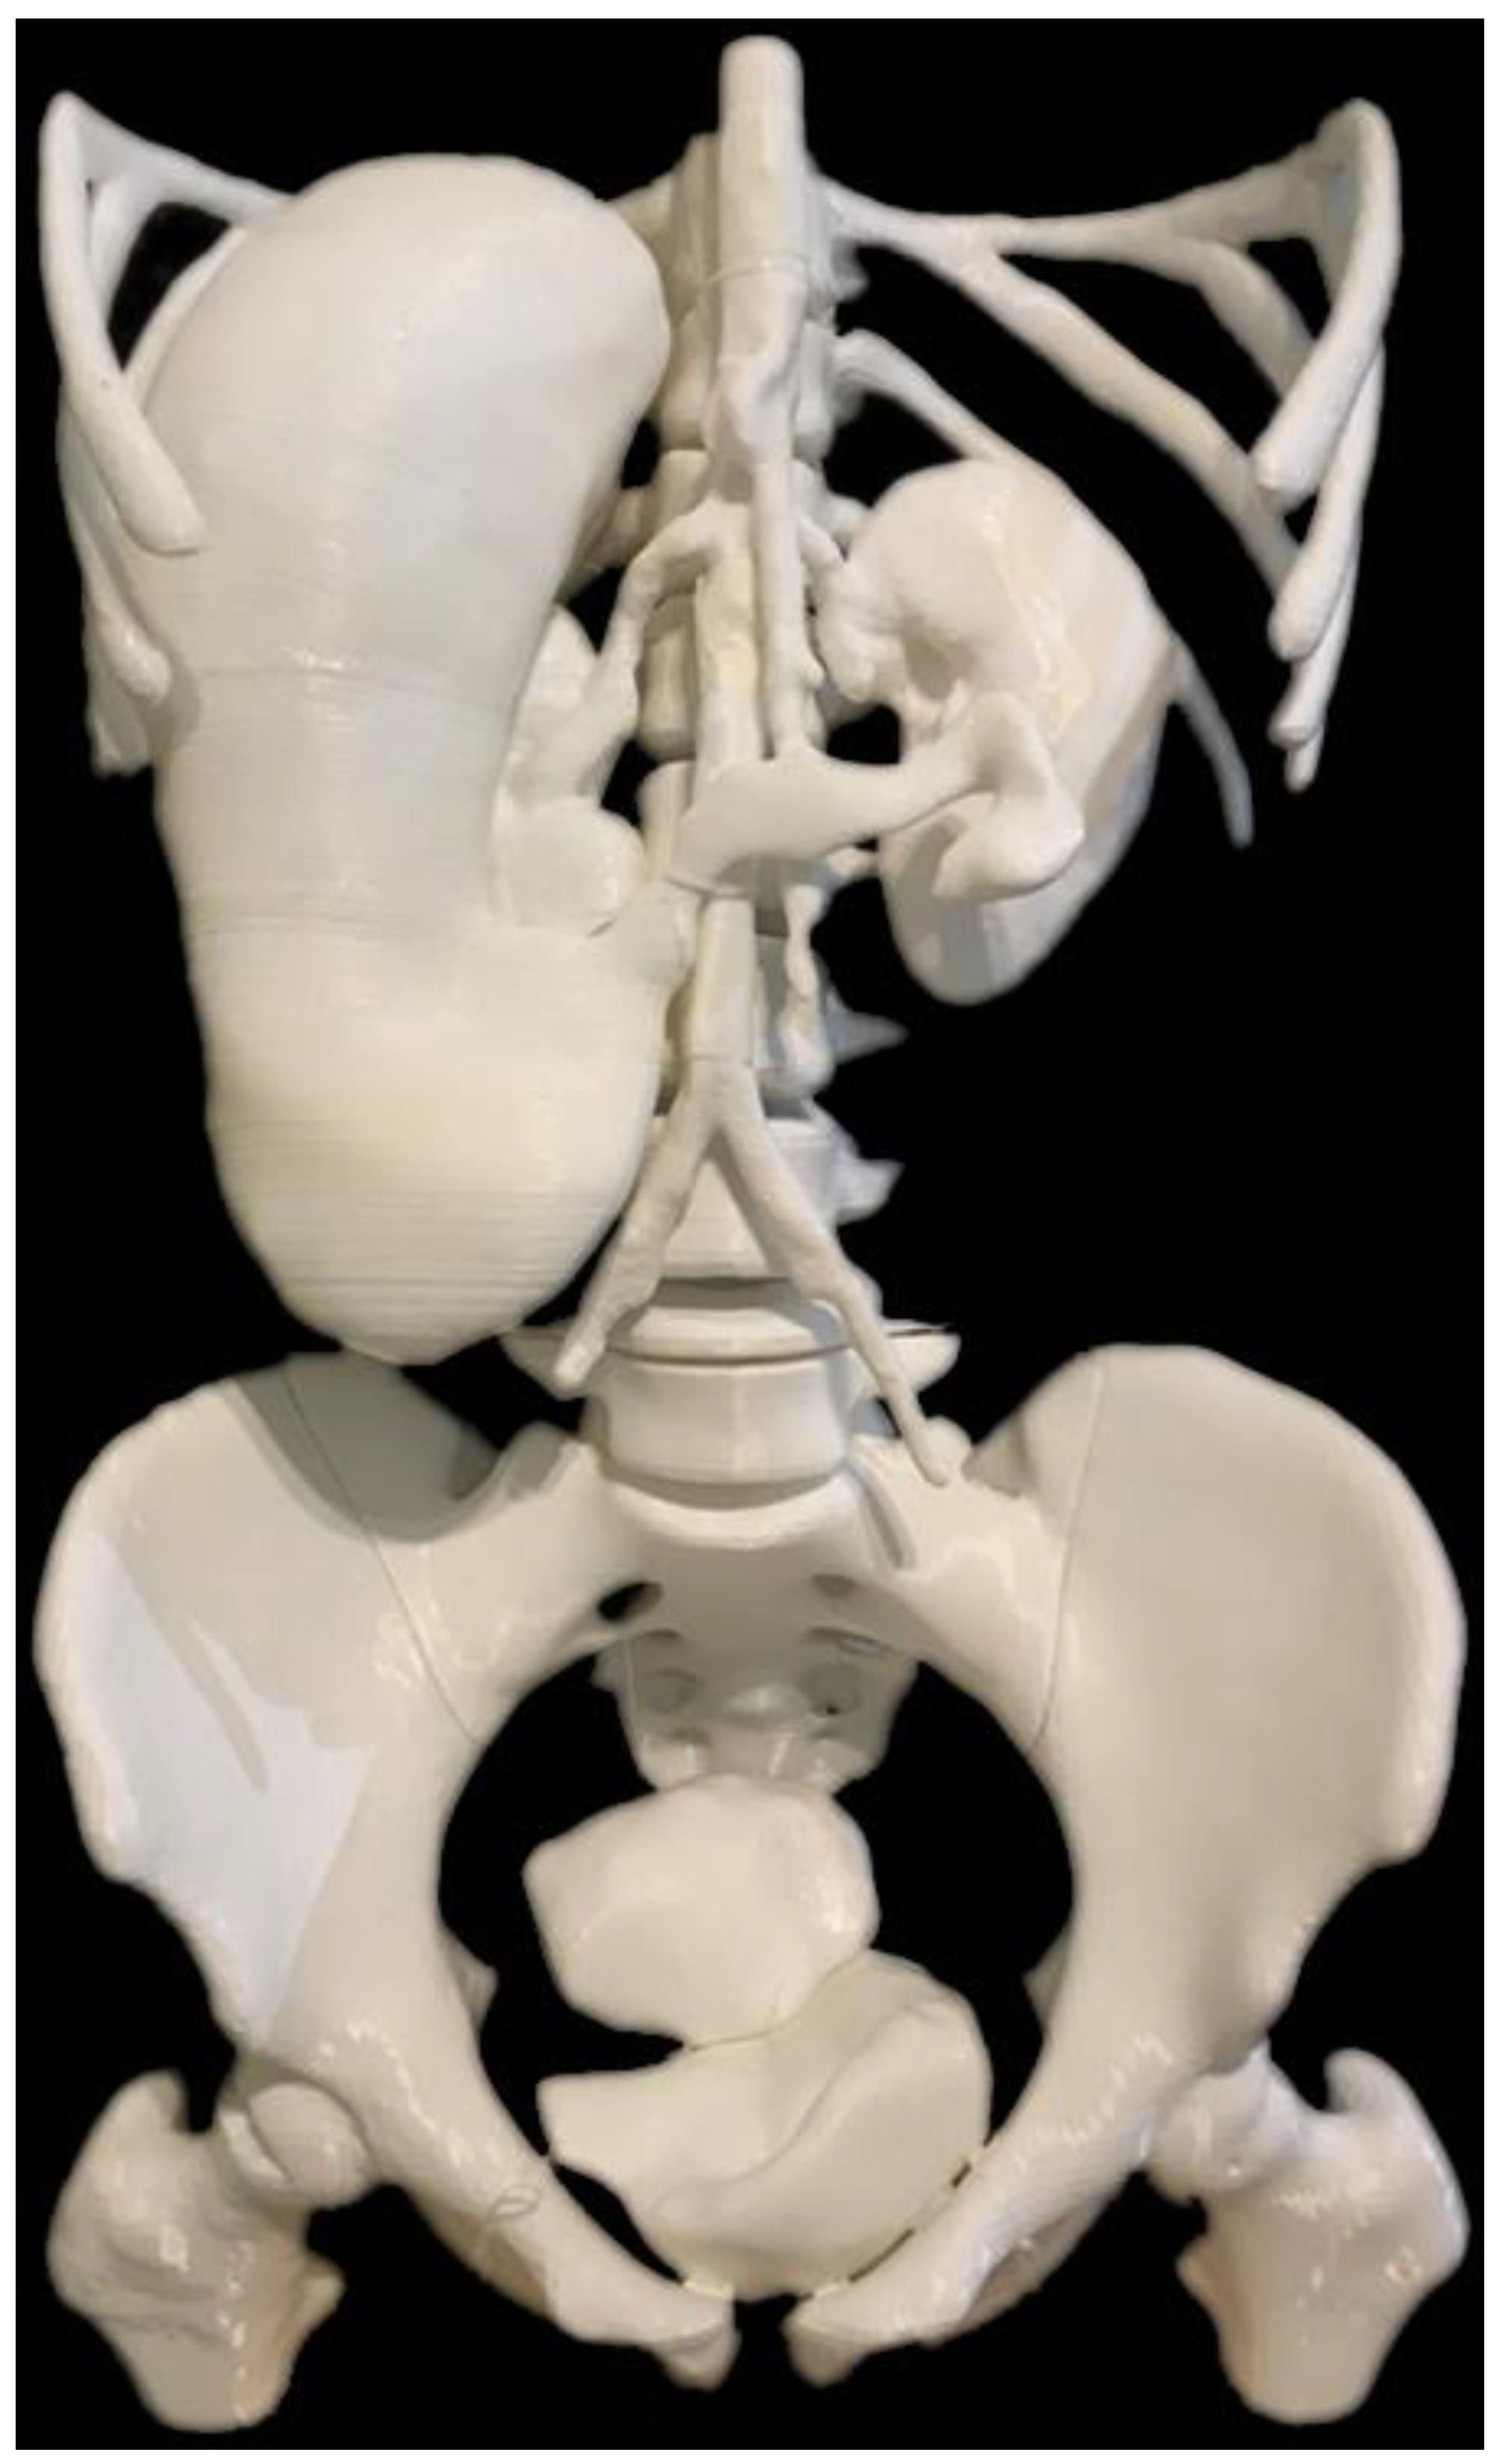

5.7. 3D-Printed Models of Abdominal and Pelvic Organs

- Etherton, D.; Tee, L.; Tillett, C.; Wong, Y.H.; Yeong, C.H.; Sun, Z. 3D visualization and 3D printing in abnormal gastrointestinal system manifestations of situs ambiguus. Quant. Imaging Med. Surg. 2020, 10, 1877–1883. [Google Scholar] [CrossRef]

| Abdomen and pelvis | Stomach: 1 Kidneys: 1 Spleen: 1 Bladder: 1 Uterus: 1 Skeleton: 1 | CT | Multiple organs for a case of situs ambiguus | Printer: Skeleton was printed using Raise3D N2 Plus (Raise3D, USA) Other organs were printed using Ultimaker 2+ Extended (Ultimaker BV, Netherland) Material: Skeleton: PLA Other organs: TPU 95A Cost: USD 55 for skeleton and USD 75 for other organs | Skeleton was printed with a resolution of 12.5 μm for the x and y-axis planes and 10 μm for z-axis plane Other organs were printed at a resolution of 12.5 μm for the x, y and z-axis plane Time: Skeleton: ~250 h Other organs: ~250 h |